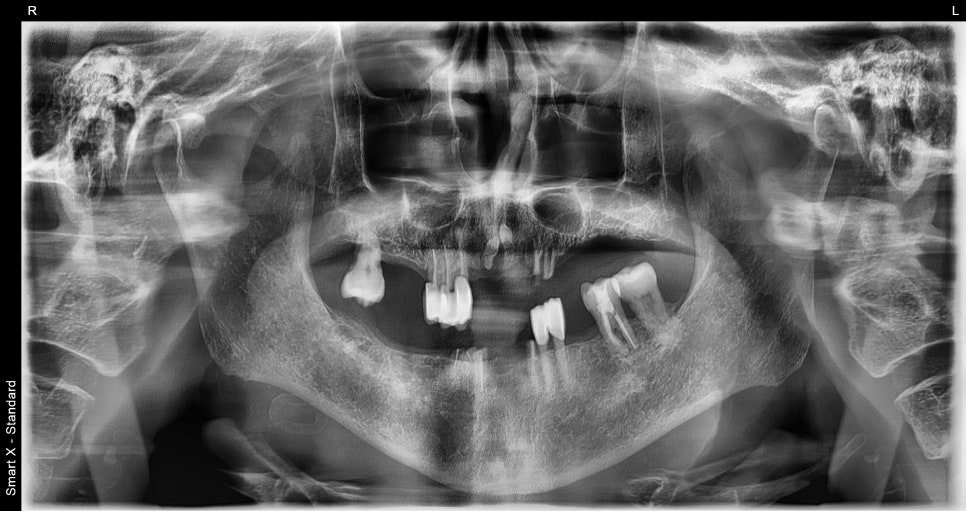

As a result of the diagnosis, the upper jaw required extraction of all remaining natural teeth followed by fabrication of a complete denture.

Although there were still some remaining teeth in the lower jaw,

for stable denture support,

we planned to place two insurance-covered implants

and then fabricate a partial denture.

📌 Before Denture Treatment

– Upper jaw: severe tooth mobility, poor fit of existing denture

– Lower jaw: insufficient partial denture retention, load burden on the gums